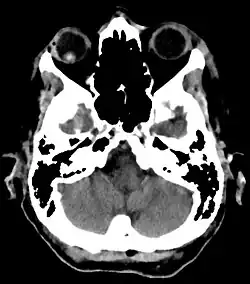

Die Linsenluxation (Luxatio lentis) oder Linsenektopie ist eine Verlagerung (Ektopie) der Augenlinse in die vordere Augenkammer oder in den Glaskörperraum. Dies kann teilweise (Subluxatio lentis) oder vollständig geschehen.

Die Linse ist durch den fehlenden Zug der Zonulafasern verkleinert und abgerundet. Sie ist im Bezug auf die optische Achse und der Pupillenmitte nicht mehr zentriert. Bei Syndromen (Marfan oder Marchesani) kann sie nach oben verlagert sein, bei primärer Zonulainsuffizienz (insbesondere beim Pseudoexfoliationssyndrom) eher nach unten. Bei Fehlen von Zonulafasern z. B. durch Traumata (insbesondere typisch sind Kuhschwanzverletzungen) bestehen Zitterbewegungen (Phakodonesis). Wenn die Linse vollständig luxiert ist, besteht ein Aphakiestatus mit einer Hyperopie (bei normaler Augapfellänge zwischen 10 und 16 Dioptrien). Die Linse findet man dann im Glaskörperraum, seltener auch in der Vorderkammer.